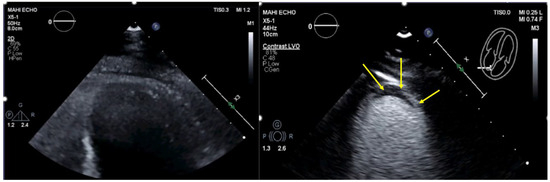

| Imaging method | Low-MI-contrast-specific imaging and intermediate-MI-contrast-specific imaging |

| Imaging planes | standard apical views additional zoomed views sweeps through the region of the suspected thrombus |

| Sector depth/width | Entire LV + 1/3 LA to assess global/regional LV function, zoomed views of the region with the suspected thrombus |

| Focus | At the depth of the suspected thrombus |

| Gain | Adjust to avoid obscuring the thrombus by intensive opacification of the cavity |

| Contrast application | bolus injections |

| Typical findings | 1. echofree mass 2. present in two different imaging planes 3. lump or laminar shape different from trabeculations’ documented size (two orthogonal diameters in at least one of the views), location, type (laminar vs. lump, single vs. multiple), surface (smooth vs. irregular) and mobility |

| DD tumor vs. thrombus | Opacified (vascularized) masses are suggestive of tumors; the vascularization can be demonstrated with myocardial perfusion imaging. CAVEAT: There are malignant tumors which appear avascular on CEUS. Tumors often are attached to normal myocardium. |